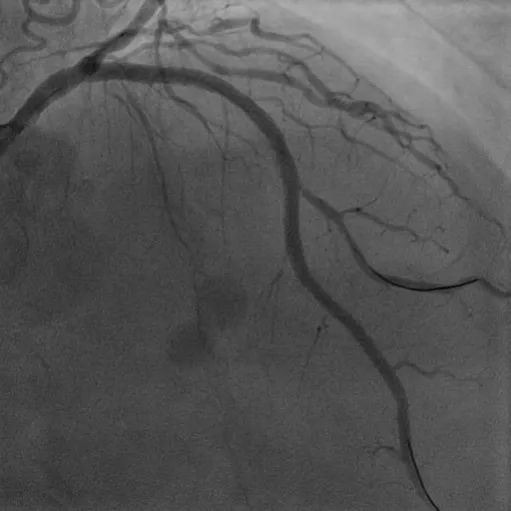

病例2

CTO病变:患者74岁男性,主因胸痛10余天,憋气1周余,加重2天入院,既往高血压、糖尿病病史、长期吸烟史。诊断急性非ST段抬高型心肌梗死、心力衰竭。强化用药改善心功能后择期行冠脉造影示LAD为CTO,RCA近段CTO病变、全程钙化影,圆锥支向LAD远端提供侧支循环。患者拒绝CABG治疗,决定开通RCA CTO。但患者RCA严重钙化,GW在微导管支持下通过CTO段,但应用普通球囊预扩后,无法送入IVUS导管,遂果断选择GuideZilla支持下Shockwave冲击波球囊治疗,成功植入支架,手术效果良好,为进一步解决LAD病变奠定了基础。